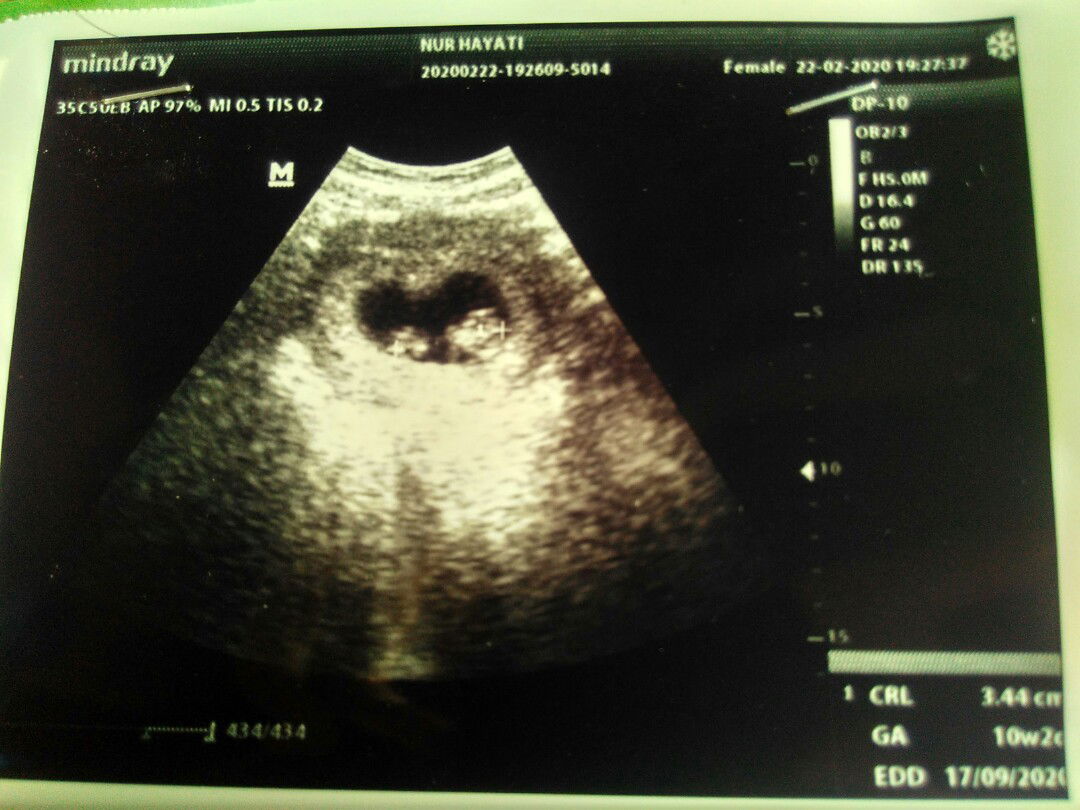

usg

Kemaren sabtu usg, uk pas 10week. Tp kok belum ada denyut jantung ya? Kata dokternya wajar, emang belum. Tp diaplikasi harusnya udah ada sejak uk 8minggu??